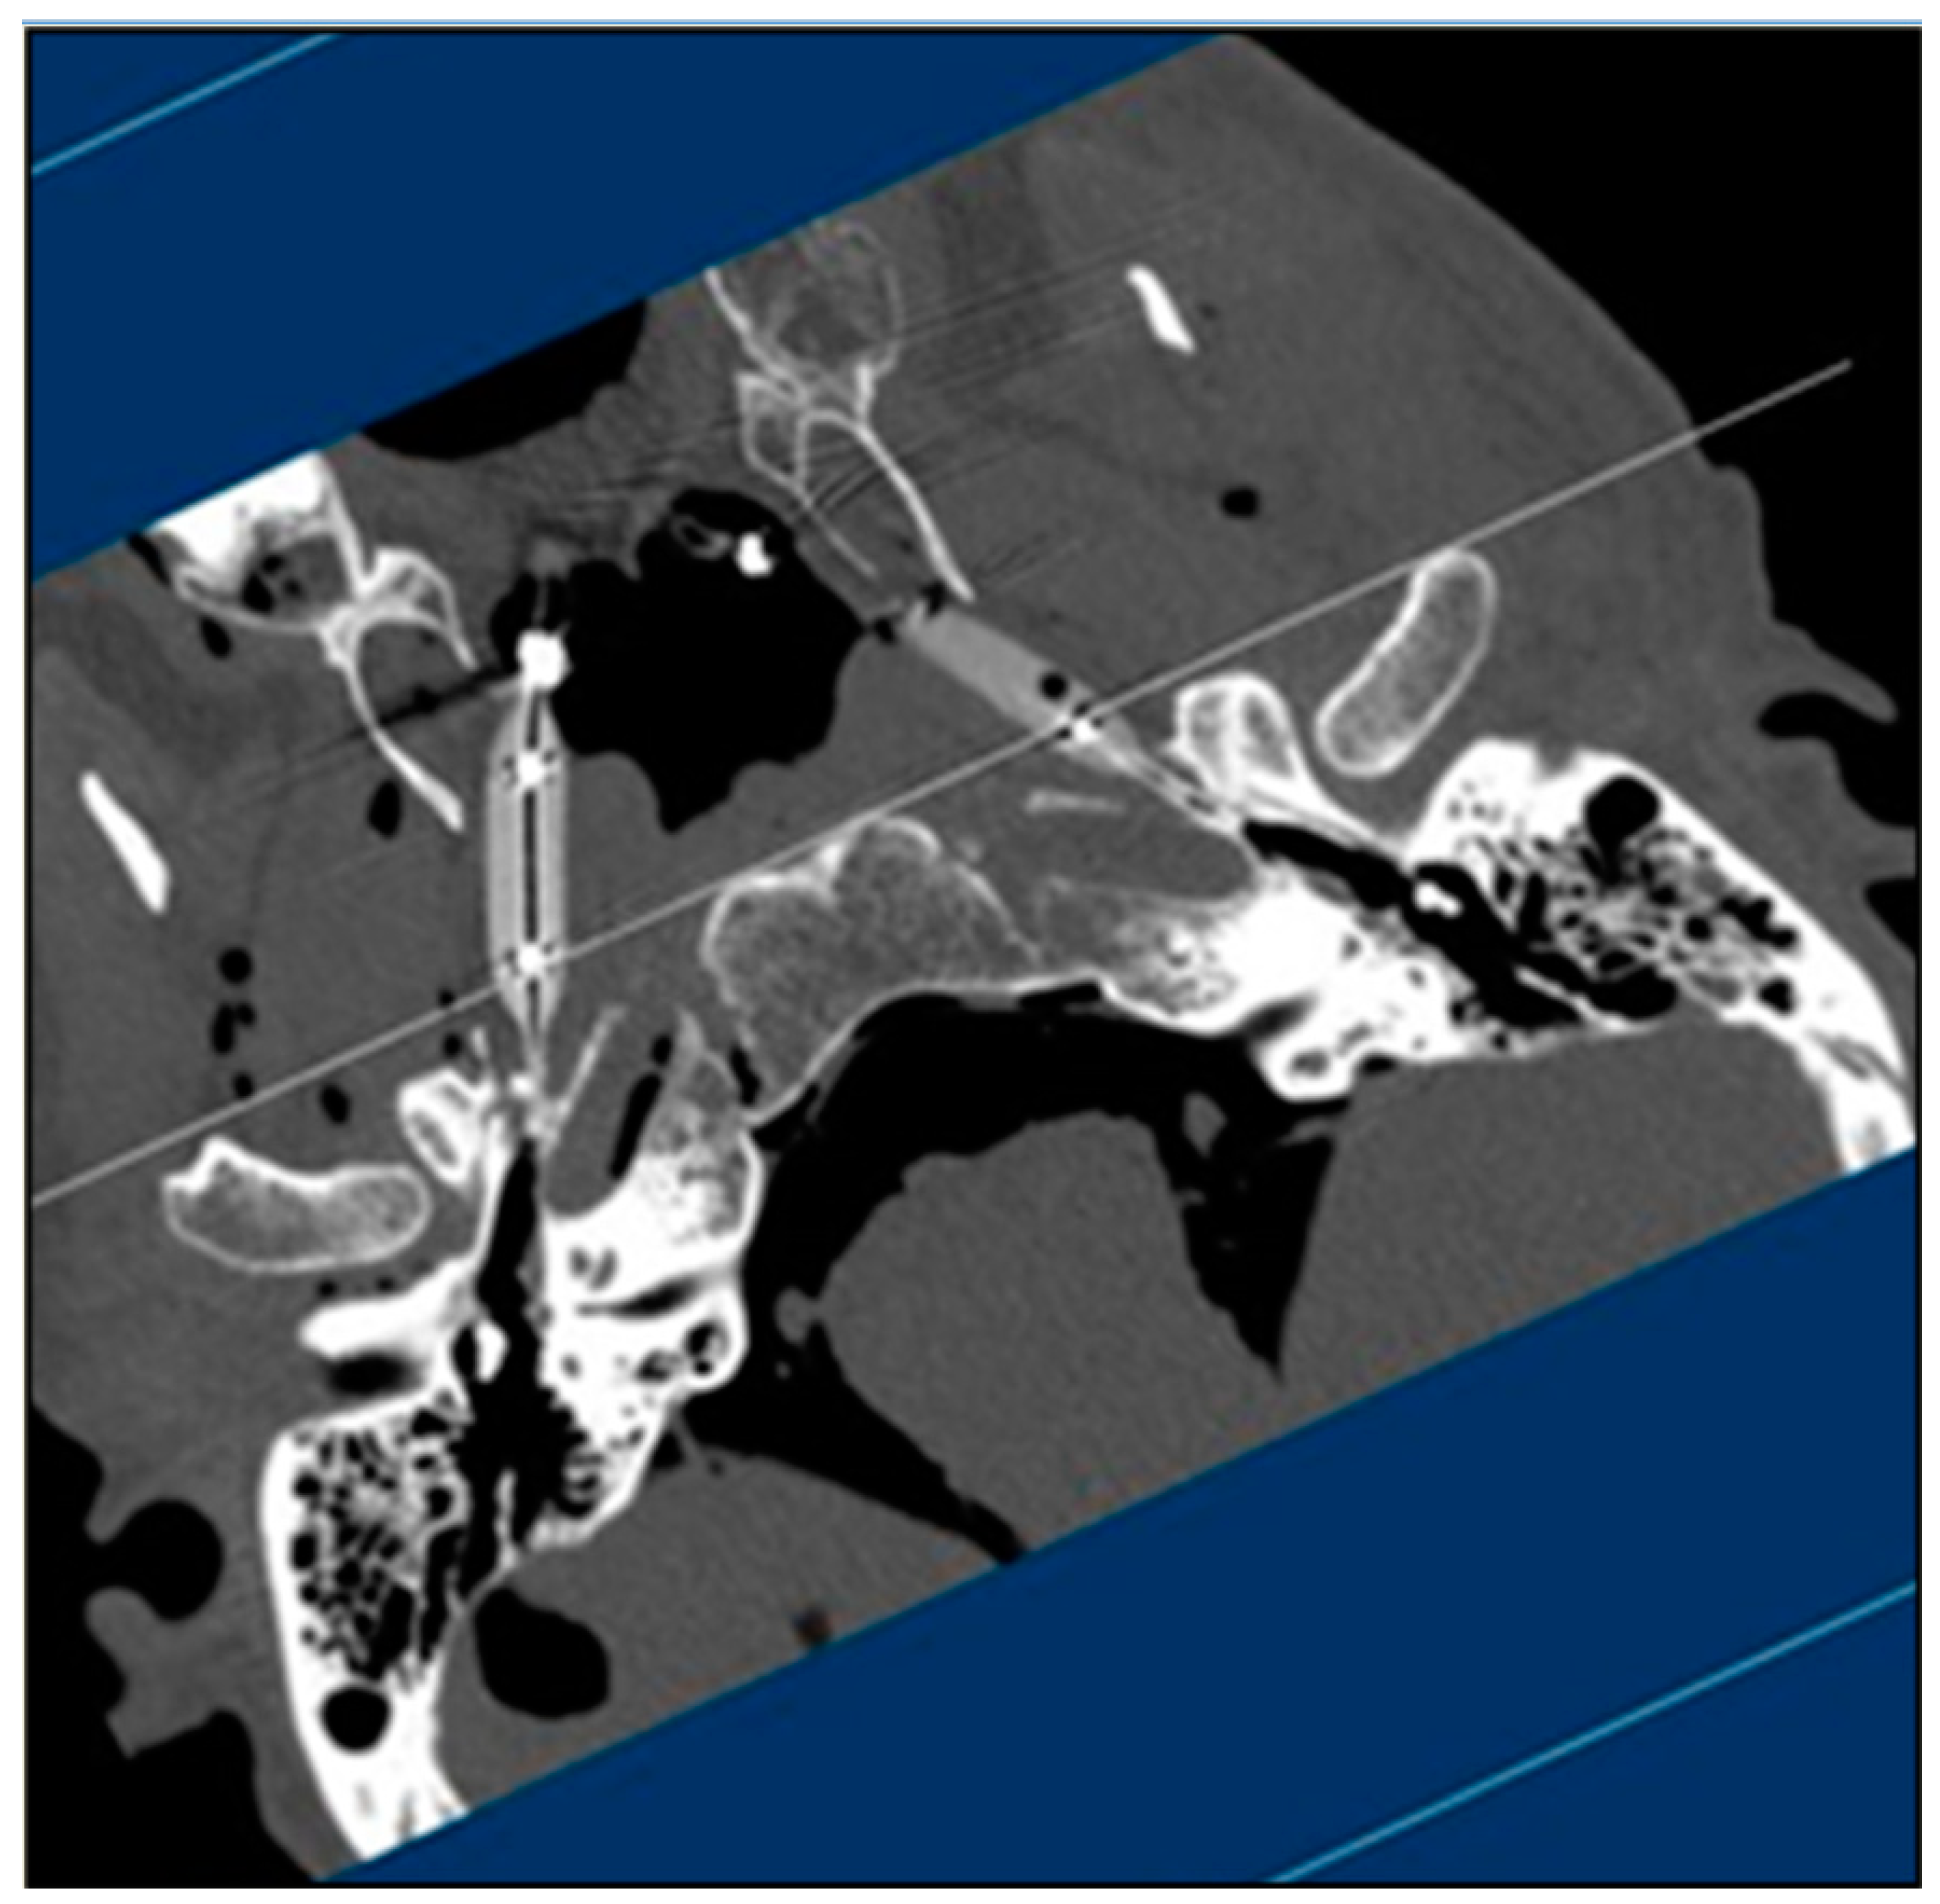

3. Results